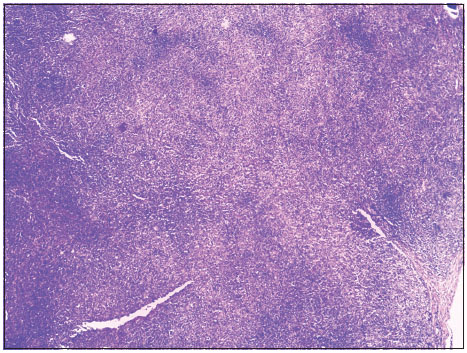

| Figure 1 Malignant adnexal skin tumor. Low‑power photomicrograph showing central cystic area with tumor cells. (H and E, ×40)